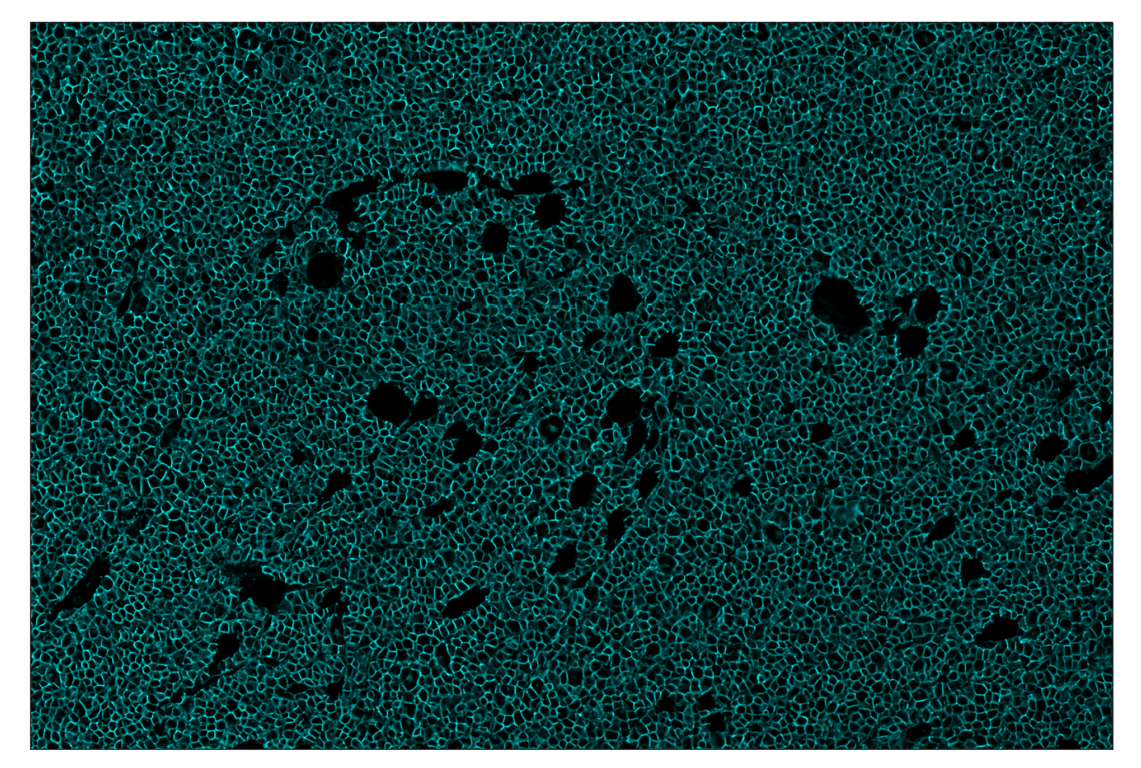

SignalStar™ multiplex immunohistochemical analysis of paraffin-embedded mouse thymus using CD20 (E3N7O) & CO-0134-488 SignalStar™ Oligo-Antibody Pair #18644 (green). All fluorophores have been assigned a pseudocolor, as indicated. Staining was performed on the BOND RX autostainer by Leica Biosystems.

Immunohistochemistry Image 2: CD20 (E3N7O) & CO-0134-594 SignalStar<sup>™</sup> Oligo-Antibody Pair